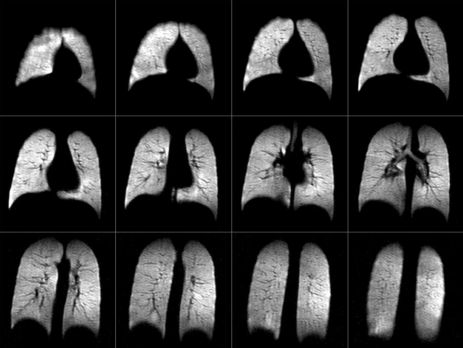

This study took advantage of the high polarization of MagniXene®

to explore the dynamics of xenon uptake

into the lung parenchyma and blood in rabbits.

The Chemical Shift of xenon allows for distinguishing NMR frequencies

between gas phase (GP) and dissolved phase (DP)

and separating their MRI images.

Dr. Kai Ruppert and his colleagues explored the time evolution

of the gas-exchange in rabbit lungs, in healthy subjects and a lung disease model.

MagniXene® single-breath MR image of a 22 y.o. female healthy volunteer. 0.7L bolus, voxel size =3.1 x 3.1 x 10mm. GRE image acquired using the Siemens Tim Trio at the Center for In-Vivo Hyper-polarized Gas Studies at the University of Virginia.

Image credits: T. A. Altes, G. W. Miller, J. P. Mugler, III, K. Ruppert